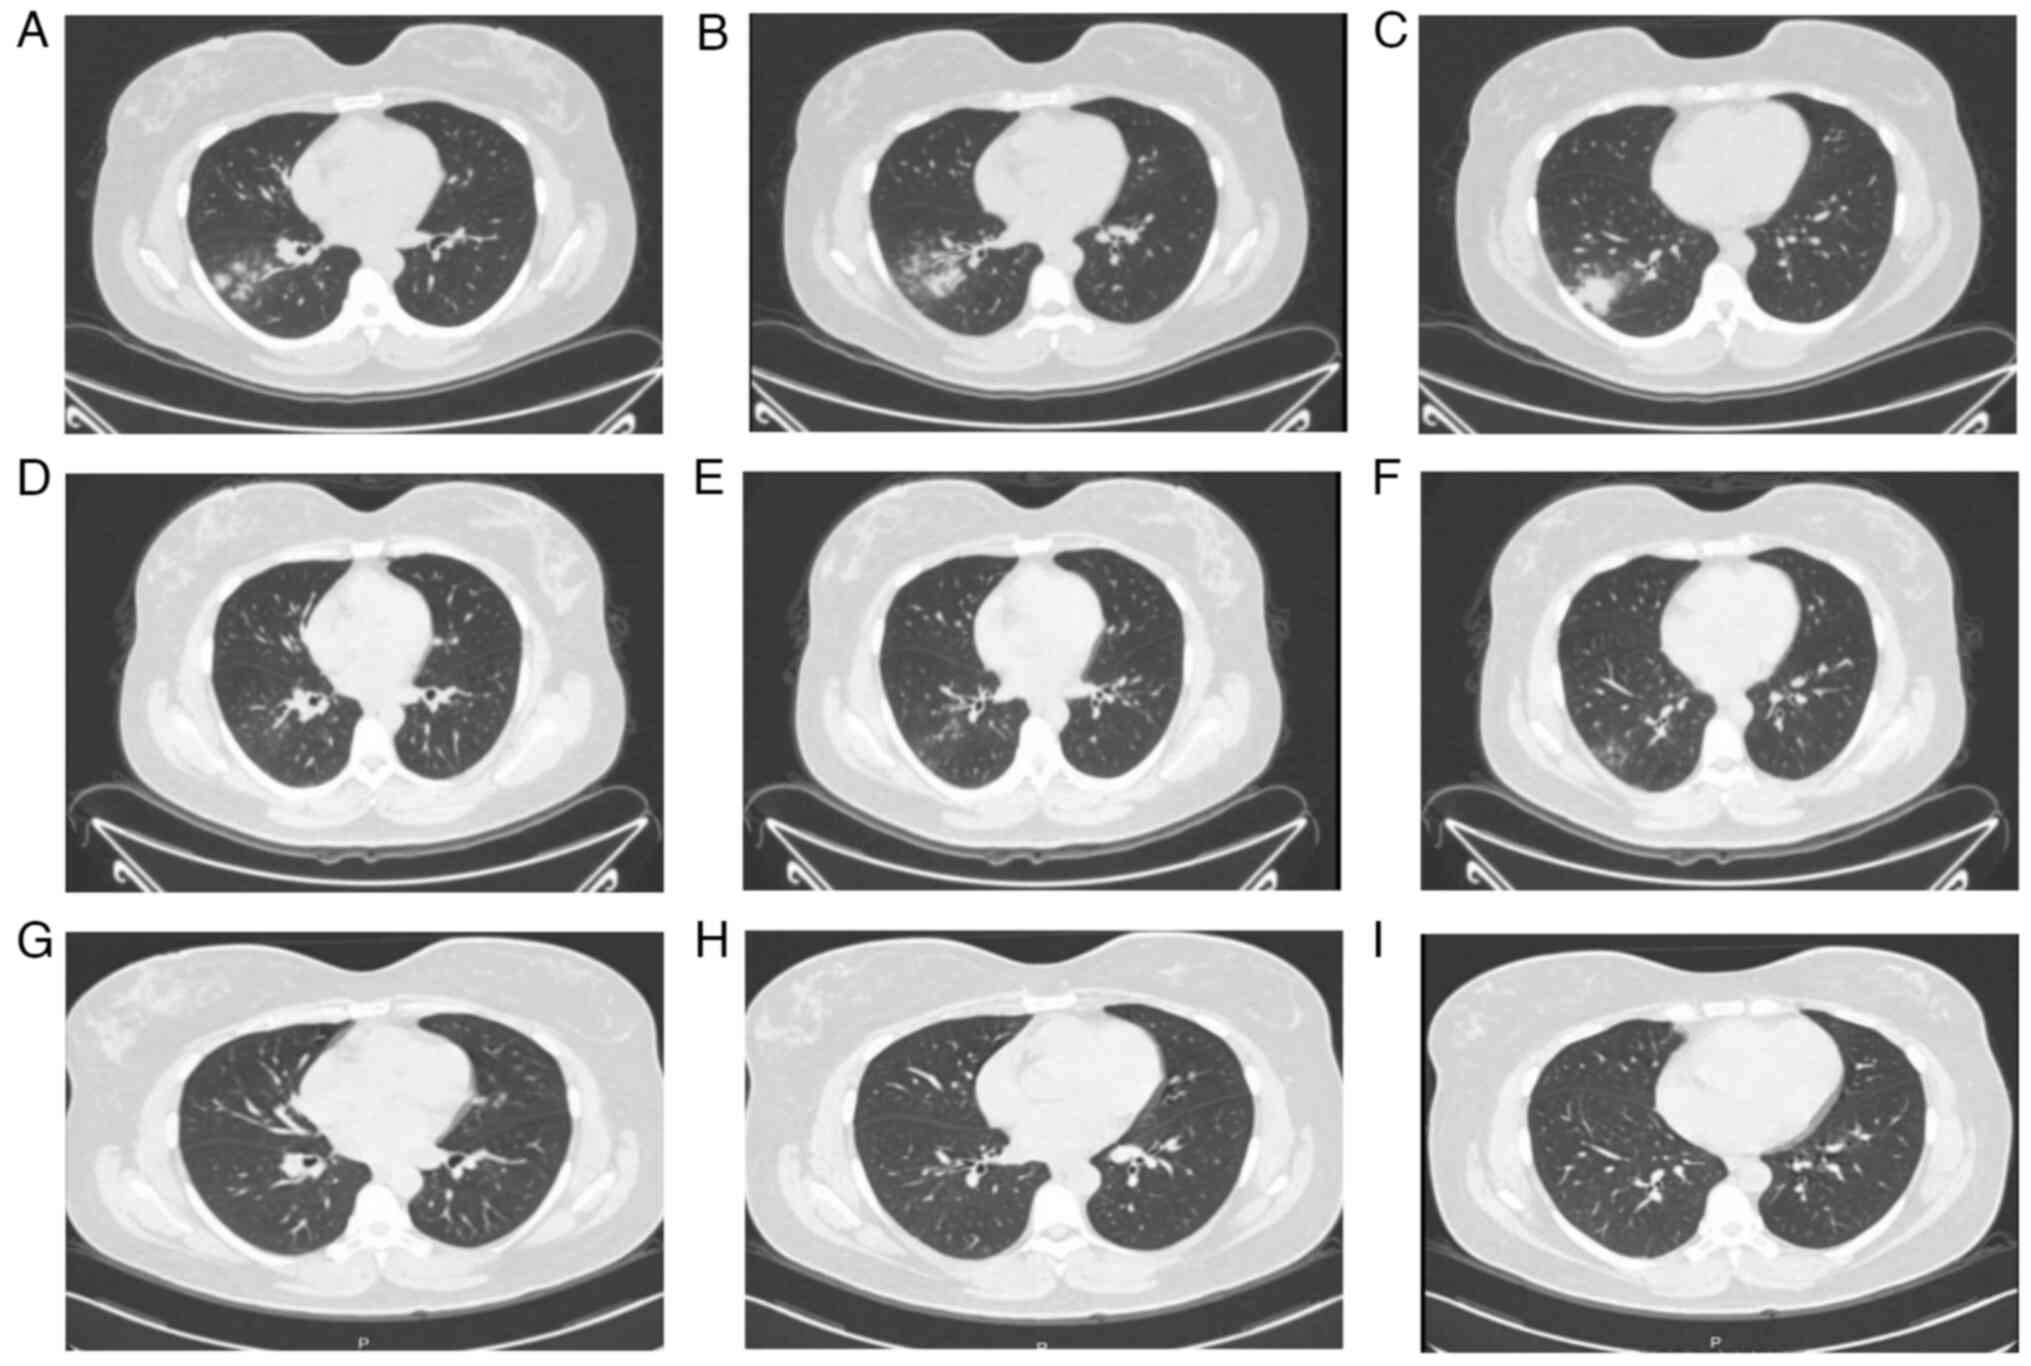

A 53-year-old male presented to the Second Affiliated Hospital of Chongqing Medical University (Chongqing, China) outpatient clinic with persistent chest pain on the right side that was aggravated by inspiration, accompanied by dizziness, headache, cough, and white mucous sputum, with progressive aggravation of the symptoms. The patient was admitted to our outpatient clinic with the condition of ‘Chest pain to be investigated’ (July 2023). Since the onset of the disease, the mental health and appetite of the patient were fine, his bowel and urine were normal and there was no significant change in his weight. Past history was physically healthy. A physical examination of the heart, lungs and abdomen revealed no abnormalities. On the same day as presentation, a computed tomography (CT)-enhanced examination of the chest revealed (Fig. 1A-C): i) Possible infectious lesions in both lungs; ii) multiple enlarged lymph nodes in the hilar and mediastinum of both lungs; iii) multiple air-containing cystic cavities in both lungs; iv) minor effusions in the pleural cavities bilaterally; and v) sclerosis of the aorta and coronary arteries.

Figure 1

Comparison of chest CT in patient 1. (A-C) Chest CT in July 2023. (D-F) Chest CT 2 weeks later. (G-I) Chest CT in August 2023. The lesions were more clearly absorbed in August compared with at the first CT scan in July.

After treatment, the chest CT was reviewed in July 2023 (Fig. 1D-F) and August 2023 (Fig. 1G-I), respectively, and significant improvement of the lesion was observed.